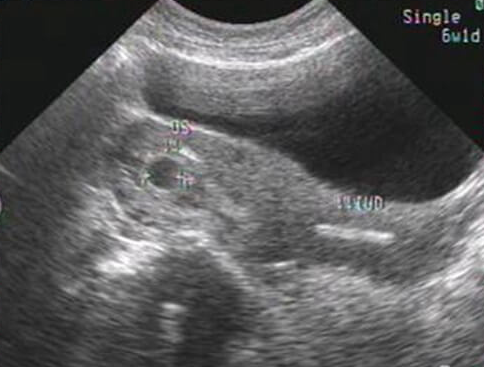

试管婴儿治疗中,空孕囊(即胚胎停育后仅存空囊结构)是许多家庭不愿面对的结果。尽管空孕囊的发生与多种因素相关,但以下五类人群因生理、环境或遗传因素,风险显著高于普通人群。